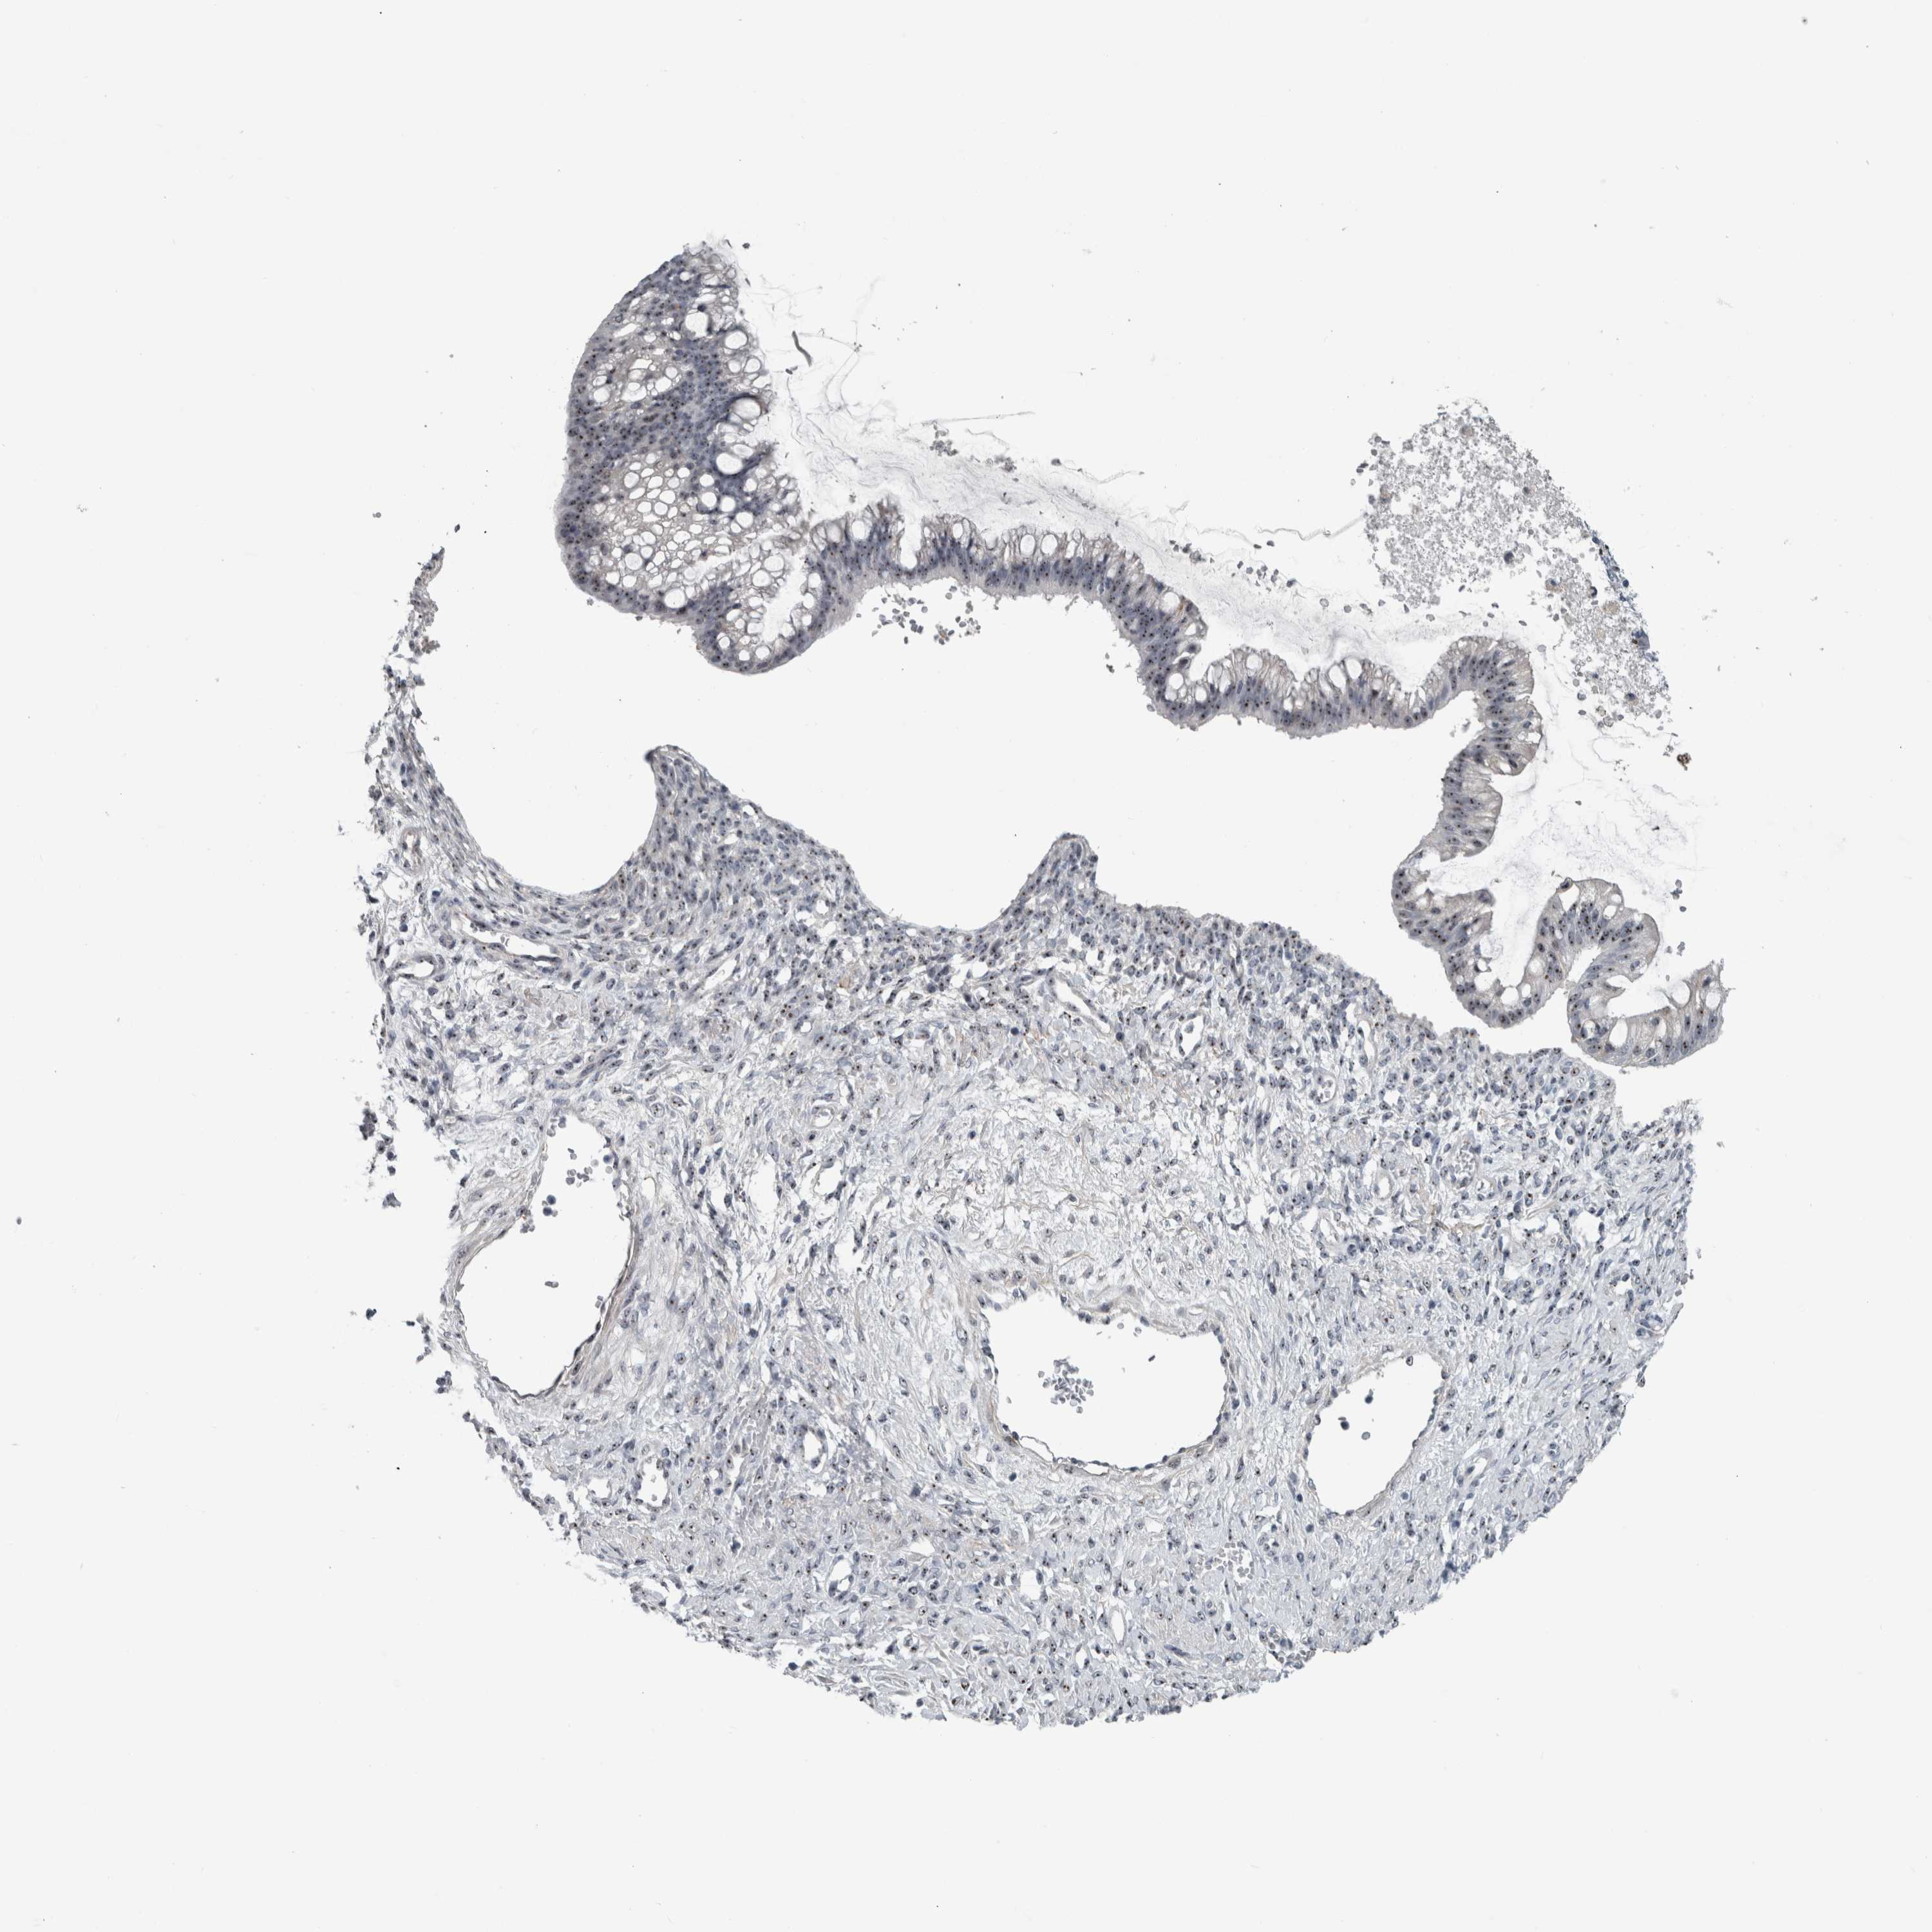

OVARIAN CANCER - Protein expressioni

A mouse-over function shows sample information and annotation data. Click on an image to view it in a full screen mode. Samples can be filtered based on level of antibody staining by selecting one or several of the following categories: high, medium, low and not detected. The assay and annotation is described here.

Note that samples used for immunohistochemistry by the Human Protein Atlas do not correspond to samples in the TCGA dataset.

Antibody stainingi

Antibody staining in the annotated cell types in the current human tissue is reported as not detected, low, medium, or high, based on conventional immunohistochemistry profiling in selected tissues. This score is based on the combination of the staining intensity and fraction of stained cells.

Each image is clickable and will lead to virtual microscopy that enables deeper exploration of all samples and also displays staining intensity scores, fraction scores and subcellular localization as well as patient and tissue information for each sample.

Antibody HPA025936

Staining

High

Medium

Low

Not detected

Intensity

Strong

Moderate

Weak

Negative

Quantity

>75%

75%-25%

<25%

None

Location

Nuclear

Cytoplasmic/membranous

Cytoplasmic/membranous,nuclear

Cystadenocarcinoma, serous, NOS

Carcinoma, endometroid

Cystadenocarcinoma, mucinous, NOS

Carcinoma, NOS